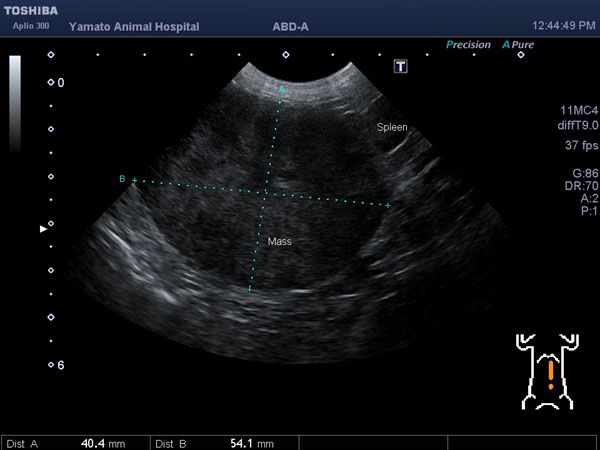

ワンちゃんが乳腺にできた複数のシコリを気にされて来院されました。bilateral mastectomyで対応しました。摘出後の病理組織検査の結果は、「R3-4間腫瘤:乳腺癌(複合型)」でそれ以外は「良性乳腺混合腫瘍」でした。無事元気に退院し、その後再発もなく経過は良好です。よかったね。